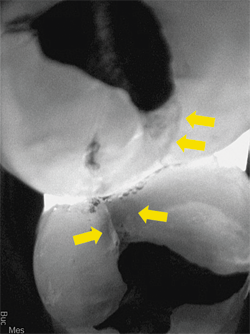

A recent example shows how a CariVu image can provide peace of mind to even the most doubting people. A patient arrived at my office with the problem of sensitivity on chewing. He told me that he did not think that the tooth was cracked. As a science education teacher at a local college, he felt confident in his self-diagnosis, and narrowed his problem down to one of two teeth. CariVu images showed him that in actuality, both teeth had cracks. The first CariVu image shows a crack on the mesial of tooth #3 (Fig. 4), and the second image shows cracks on the distal of tooth #3 and on the mesial of tooth #2 (Fig. 5). Of note is the dark area around the crack on #2 that represents the spreading caries that originate from the fracture. When faced with the evidence on the CariVu images, this skeptical science person now understood where his sensitivity was originating from, and he was eager to make the appointment for the appropriate repairs to those teeth.